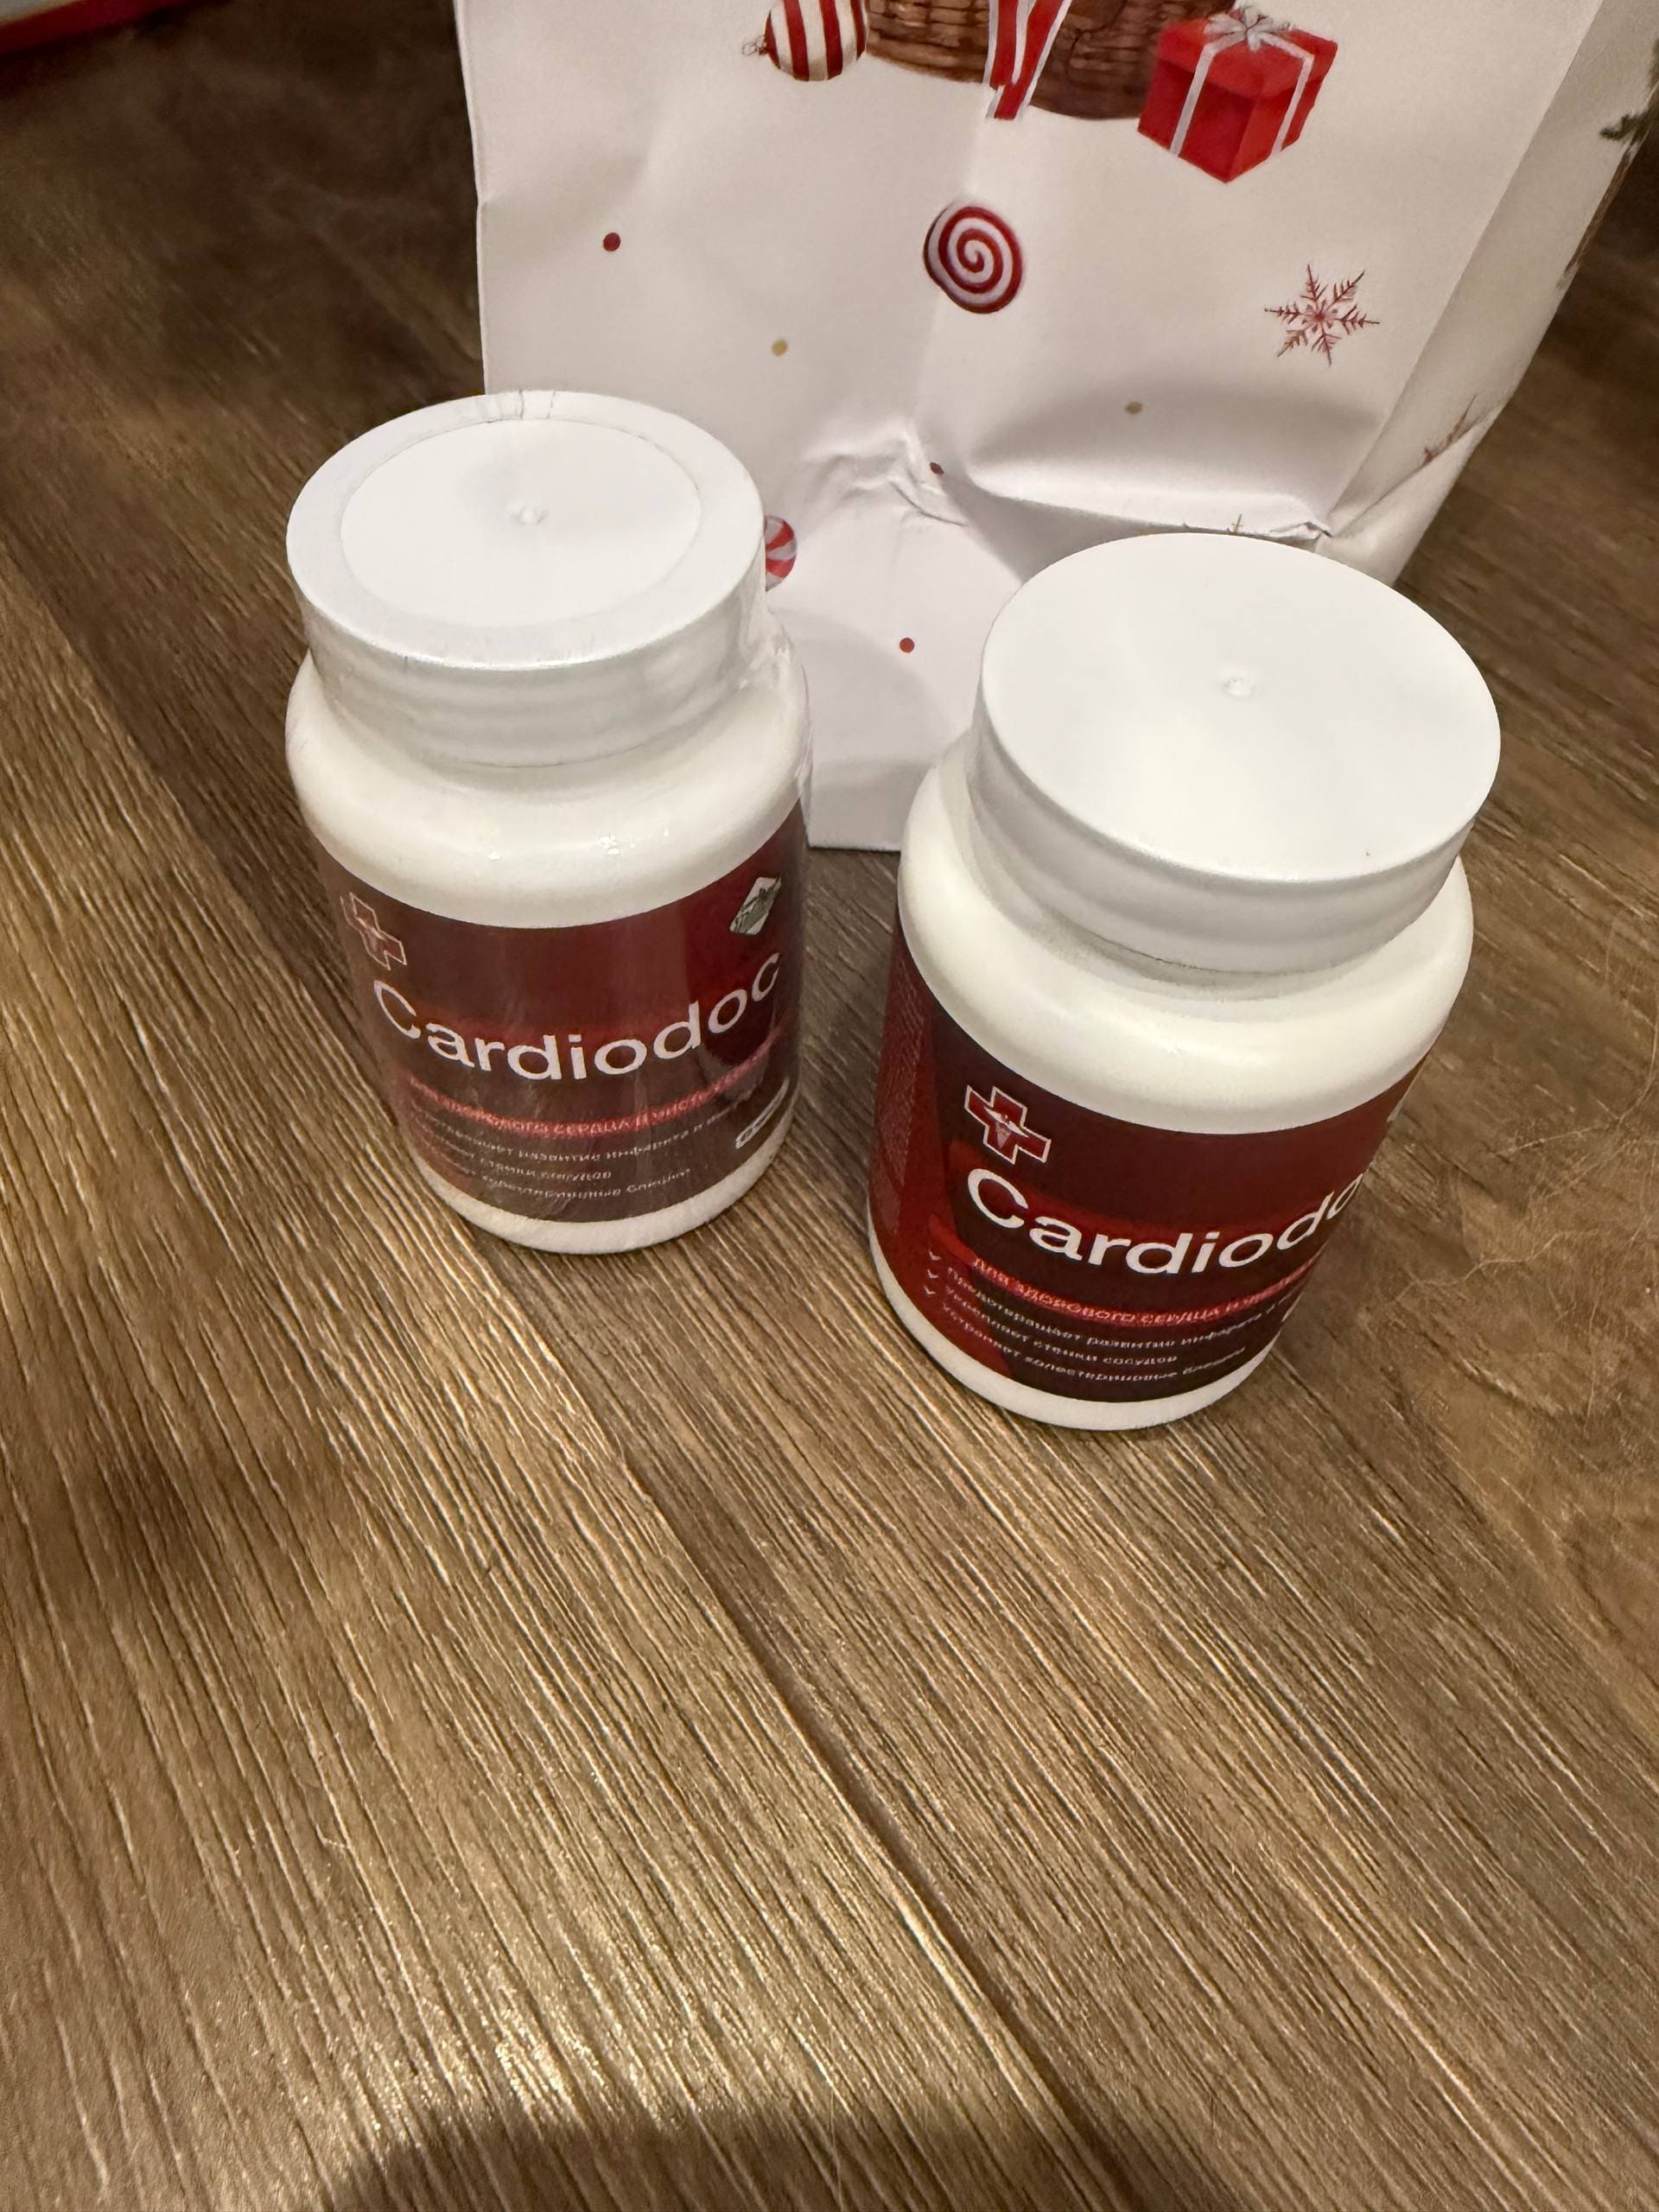

Леонид Бокерия: Да, все именно так, именно благодаря этому средству нам удалось спасти жизнь Никиты Сергеевича. Это средство называется Cardiodoc.

Оно легко может прибавить вам 10, а то и 20 лет к вашей жизни. И эта жизнь будет насыщенной во всех смыслах: Вы будете чувствовать себя бодро и энергично до старости, Ваш мозг и память будут работать безупречно, а внезапная боль в какой-либо из частей тела вряд ли когда-нибудь снова Вас побеспокоит.

Cardiodoc не вызывает побочных эффектов, в отличие от 99% других средств от гипертонии. И его действие можно сравнить только с хирургическим вмешательством.

Cardiodoc — это смесь экстрактов растений, которая не будет откладываться в ваших сосудах с другими кальциевыми сгустками, а скорее «смоет» весь мусор из вен, артерий и мельчайших капилляров. Компоненты этого средства под чистую удаляют холестерин, сгустки крови и отложения кальция — все, что мешает свободному току крови по вашему телу.

Ни одно аптечное средство не сможет очистить Ваши сосуды, которые были закупорены десятилетиями, быстрее, чем это сделает Cardiodoc. И для такой капитальной «уборки» достаточно одного или максимум нескольких курсов.

Леонид Бокерия: Да, это действительно так, но это всего лишь награда. Главное, что Никита Сергеевич жив и в прекрасном здравии. А это, конечно, заслуга не столько наша, сколько средства Cardiodoc.

Владимир Соловьев: Прошу Вас, не скромничайте. Вы сделали и продолжаете делать огромную и очень важную работу — помогаете в том числе простым людям, рассказывая о таком важном и нужно изобретении. Расскажите, пожалуйста, подробнее о том, как именно действует Cardiodoc.

За первый месяц Cardiodoc очистит ваши сосуды примерно на 70%. Удалит до 2 кг холестериновых бляшек, до 1 кг тромбов и 400 г кальциевой извести.

Cardiodoc очищает сосуды, и стабилизирует давление на годы вперед. Его не нужно принимать постоянно.

Всего за 7 недель Cardiodoc полностью восстанавливает сосуды и давление будет 120 на 80 следующие 5 лет.

Важно! Принимать средство нужно курсом, поскольку оно имеет накопительный эффект. Активные вещества в организме должны достигнуть необходимой концентрации, чтобы эффект сохранился надолго.

Cardiodoc нет в аптеках?!

Александр Мясников: К сожалению, это правда. Мы отказались платить «откаты» жадным аптечным сетям. Они хотели сделать огромную наценку, чтобы лично получать свои деньги за каждую посылку. При таких завышенных ценах курс мог обойтись покупателю в 15, а то во все 20 тыс. рублей.

Руководство аптек объяснило нам, что если человек купит курс Cardiodoc, он избавится от гипертонии и очистит сосуды, а аптеки потеряют постоянного покупателя. В других лекарствах, которые он послушно покупал каждый месяц, больше не будет необходимости. Это приведет к огромным убыткам для аптечных сетей. Именно поэтому они потребовали установить максимально возможную цену за курс.

В результате производитель Cardiodoc разорвал контракты со всеми аптеками и перешел на продажу только через Интернет. Зато именно таким образом удалось обойти множество проблем. Клиент разговаривает по телефону с куратором программы, вместе они определяют продолжительность курса, после чего клиент просто получает посылку и оплачивает ее по факту получения. Поэтому сейчас Cardiodoc намного доступнее и даже дешевле, потому что нет никаких аптечных наценок.

Наш институт совместно с производителем Cardiodocв запустил региональную льготную программу «Чистые сосуды»!

Жители регионов, участвующих в данной программе, могут получить Cardiodoc со скидкой до 100% по специальной акции.